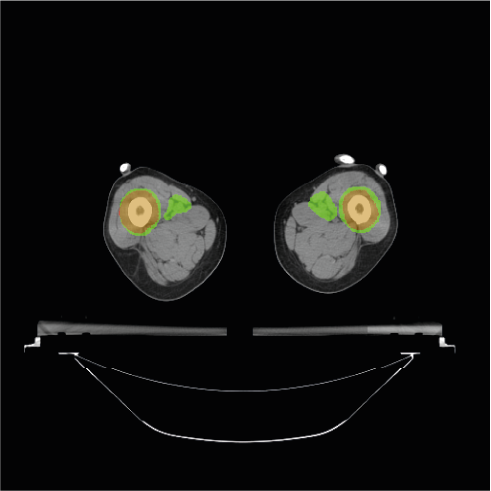

To further understand the areas where the models do not accurately segment the PTV, we provide some visual examples of the poor segmentations Figure 4. The first row of the Figure 4 shows four examples of slices poorly segmented by the BCEL model. The first slice (Figure 4a) corresponds to the head and neck area. The segmentation error in the left and right areas of the head (i.e., the green areas) may be due to conservative segmentation of the second level of neck lymph nodes in the ground truth. The standard reference point for segmenting these lymph nodes might be a slightly higher slice, but the radiation oncologist likely included the target on this slice due to the large CT thickness of 5 mm. The second slice (Figure 4b) shows an absence of hepatic portal lymph nodes. This area is subject to high anatomical variability, and due to the lack of contouring guidelines [38] in the early years of data acquisition, this area was often omitted by the radiation oncologist. In the third slice (Figure 4c), the absence of the pre-sacral lymph nodes (anterior to the sacrum) is evident. Moreover, the predicted segmentation of the external iliac lymph nodes is inaccurate. This target area is defined by adding a margin to the iliac vessels. In the fourth slice (Figure 4d), representing the legs area, the prediction fails to segment the inguinal lymph nodes, likely because these are frequently omitted by physicians. The second row of the Figure 4 shows the same slices overlayed with the predictions of the DL model. Notably, the segmentation errors of the DL model closely resemble those of the BCEL one, previously discussed. Please notice that the segmentation mistakes of DL model are very similar to the ones of the BCEL model, previously discussed. Nevertheless, a higher propensity for false negatives is discernible in the DL model’s segmentations, evidenced by the larger green regions surrounding the bones in Figure 4h and within the iliac lymph node area in Figure 4g.